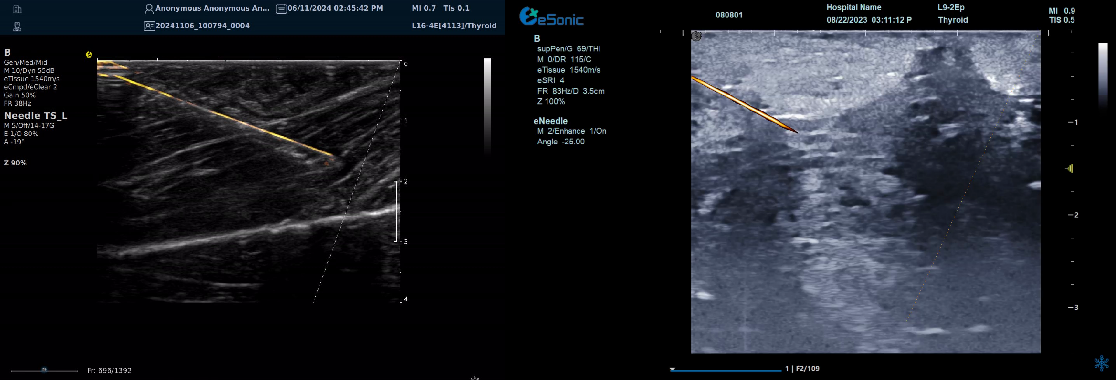

智能介入解决方案----- 穿刺针增强技术

?指示针尖位置、提高针道显示

?穿刺针智能彩色map,有效区分针尖与神经肌腱组织,

尤其在热消融时空化组织不影响针尖显示

?无磁导航:精准制导、自动追踪

?智能识别、路径预判

--引导延长线随针尖转动实时偏转

![]()